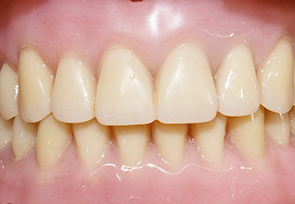

틀니 착용 모습